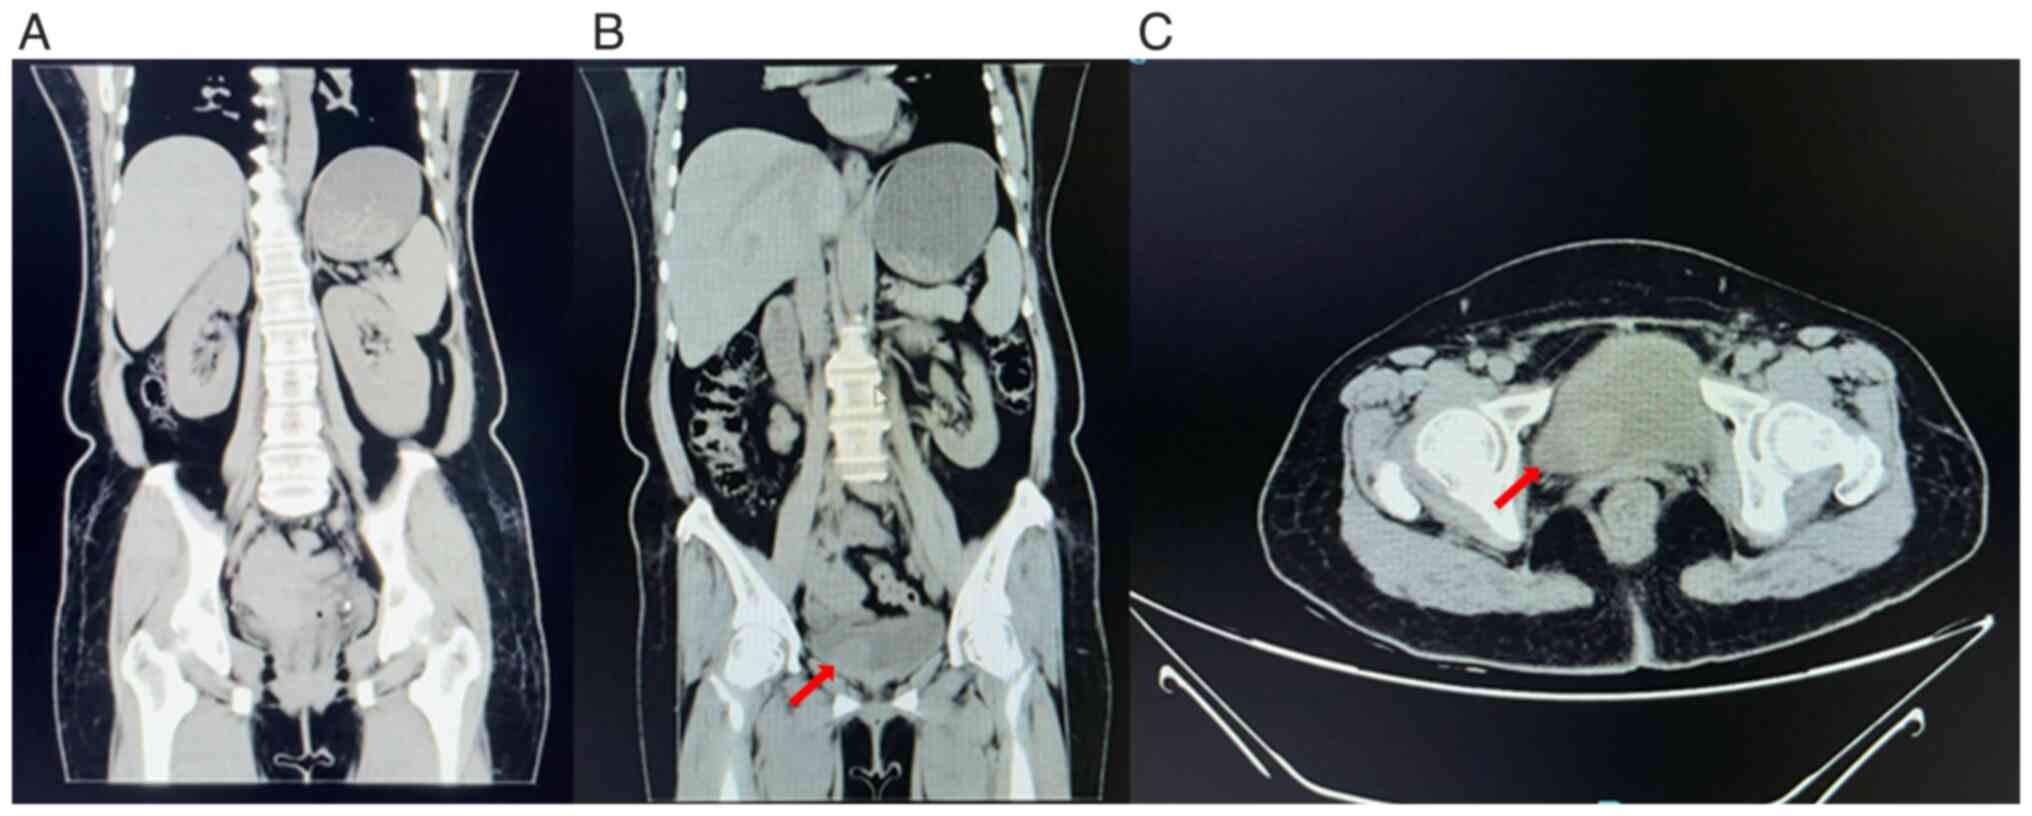

Bladder leiomyoma in the absence of symptoms: A case report and mini‑review of the literature

Figure 1